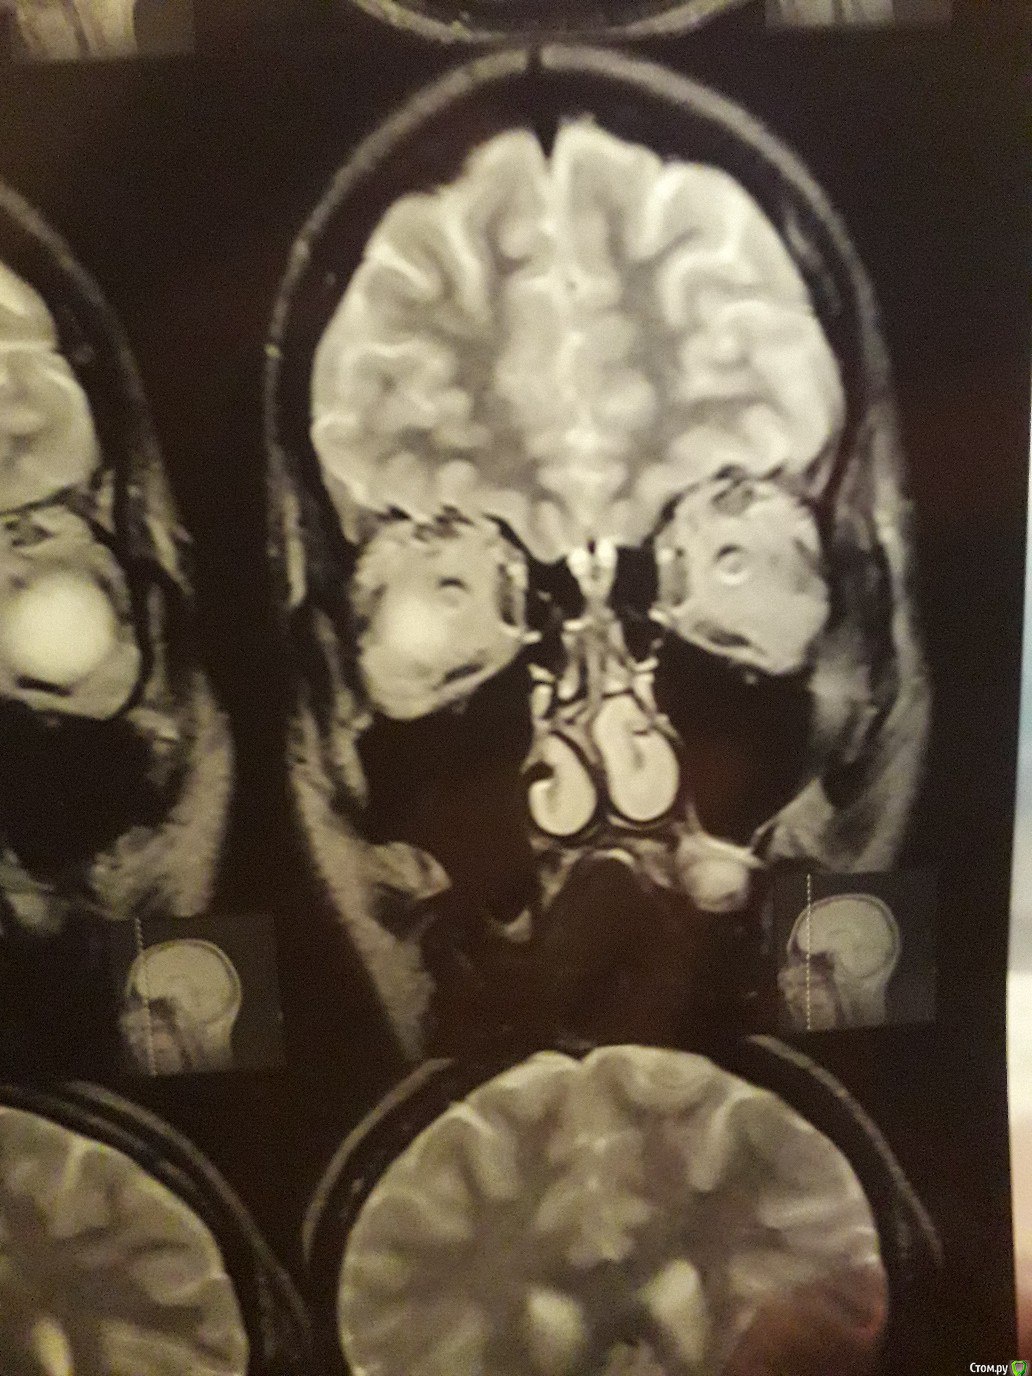

Виталий000000001 Опубликовано 30 сентября, 2017 Поделиться Опубликовано 30 сентября, 2017 Здравствуйте. На корне 26-го зуба киста вросшая в гайморову.Одни врач посоветовал удалить;Второй - не трогать и понаблюдать, если не беспокоит;А третий хирург сказал, что при удалении зуба, такая большая киста останется в кости и продолжит расти и что такое лечится только операцией на гайморовой.Подскажите что делать с кистой. Ссылка на комментарий

red_butler Опубликовано 1 октября, 2017 Поделиться Опубликовано 1 октября, 2017 По этим снимкам ничего не скажешь. Делайте кт на стоматологическом томографе 1 Ссылка на комментарий

IvanK Опубликовано 2 октября, 2017 Поделиться Опубликовано 2 октября, 2017 Перфорируется ли гайморова при удалении этого зуба?скорее нет, чем да По этим снимкам ничего не скажешь. Делайте кт на стоматологическом томографе+1 Ссылка на комментарий